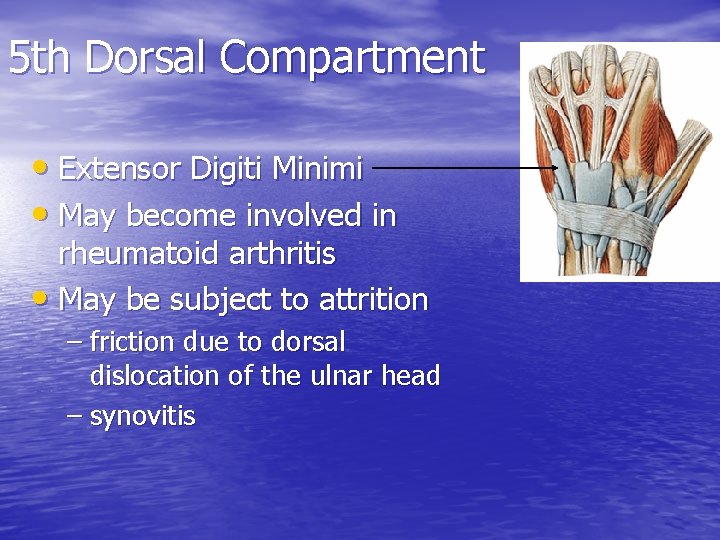

5 th Dorsal Compartment • Extensor Digiti Minimi • May become involved in rheumatoid arthritis • May be subject to attrition – friction due to dorsal dislocation of the ulnar head – synovitis